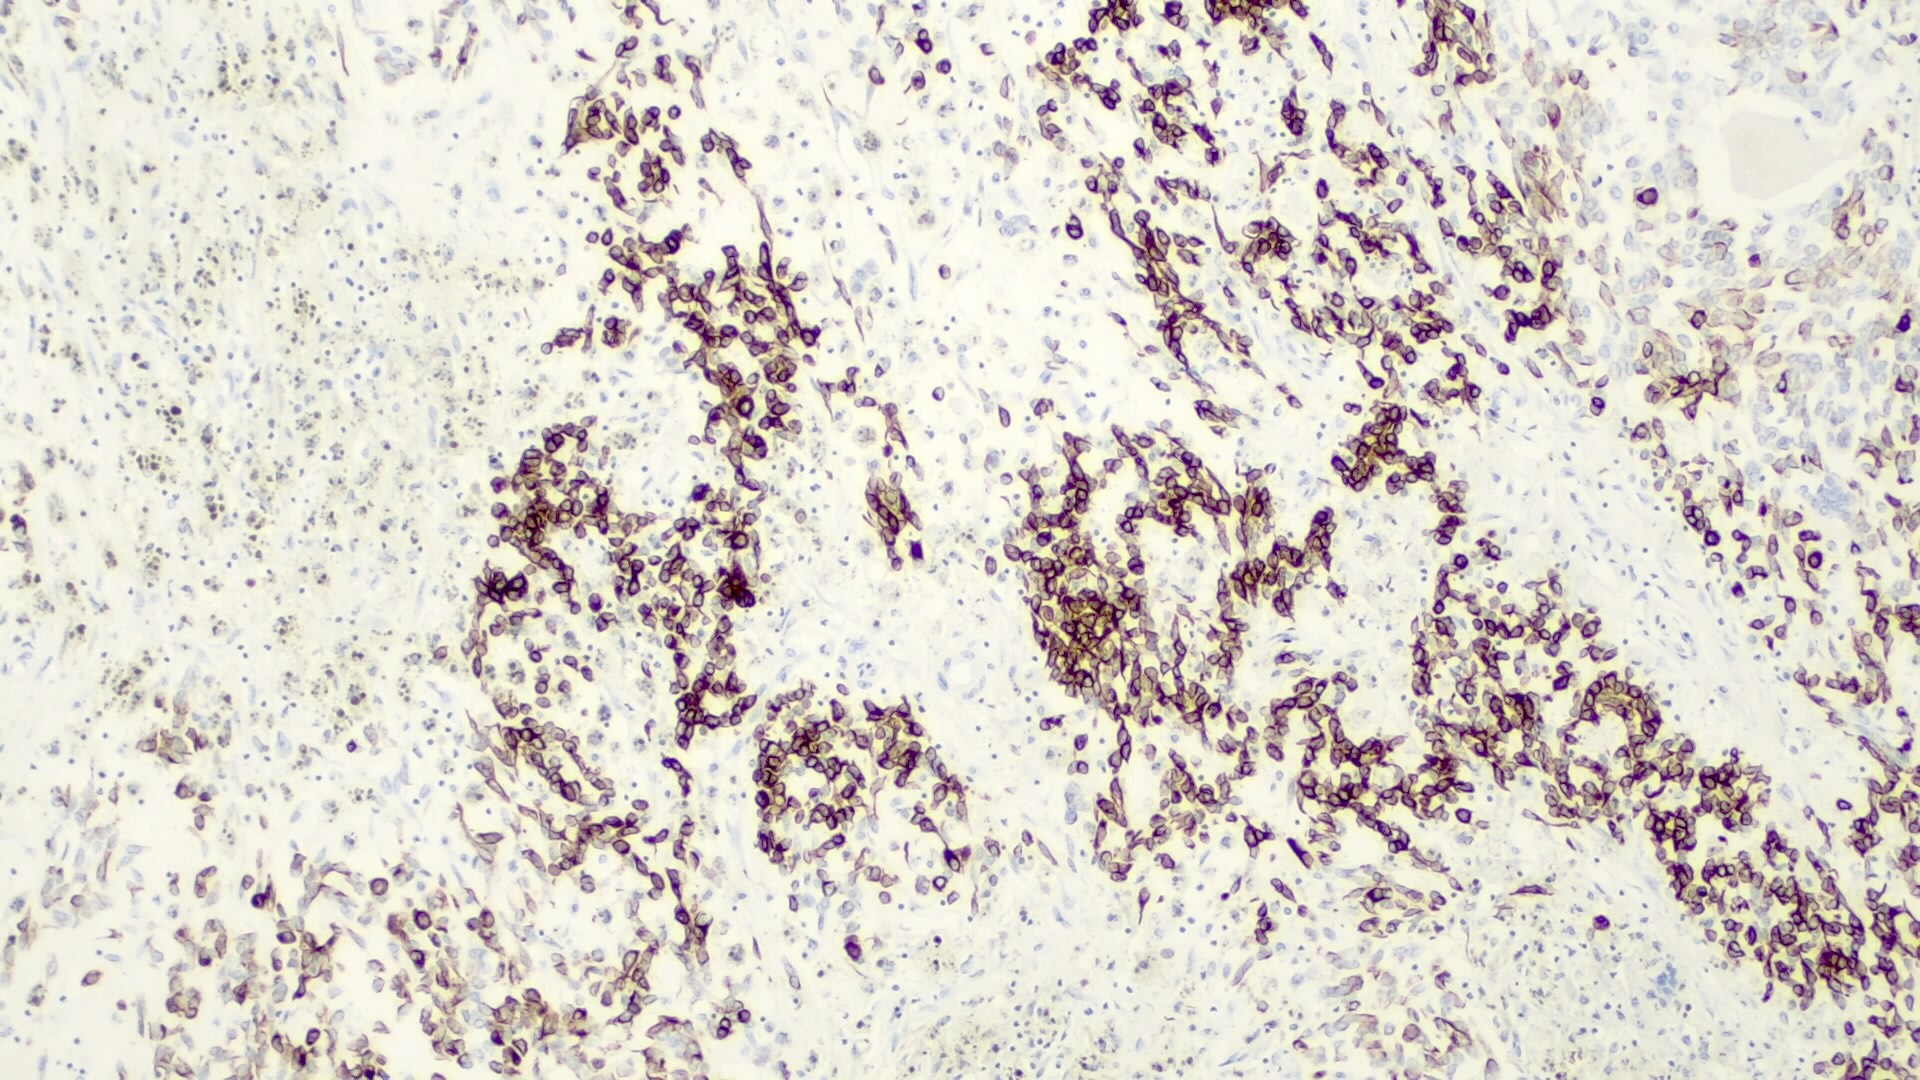

Positive stains

- Alpha fetoprotein (negative in small cell type), chromogranin (fetal, epithelial subtypes, usually focal), CK8 / 18 (fetal, epithelial subtypes), CK19 (embryonal subtypes)

- Also EMA, HepPar1 (negative in small cell type), polyclonal CEA (canalicular pattern), vimentin

- Variable hCG, occasional HMB45 and melanin

- Beta catenin (nuclear) in small cell and embryonal types, delta-like protein (DLK), glypican 3 (negative in small cell type), glutamine synthetase

Positive stains

- Frequent beta catenin and glutamine synthetase in the epithelial fetal (except the well differentiated and low mitotic subtype) and mesenchymal patterns (Pediatr Dev Pathol 2020;23:79, Biosci Rep 2019;39:BSR20192466)

- AFP in the less differentiated epithelial components

- HepPar1 in the fetal pattern

- Polyclonal CEA

- Glypican 3 in the fetal and embryonal pattern

- Pancytokeratins have variable expression (J Gastrointest Oncol 2018;9:326)

- CK7 and CK19 in the cholangioblastic pattern (J Gastrointest Oncol 2018;9:326)

- INI1 / SMARCB1 usually retained